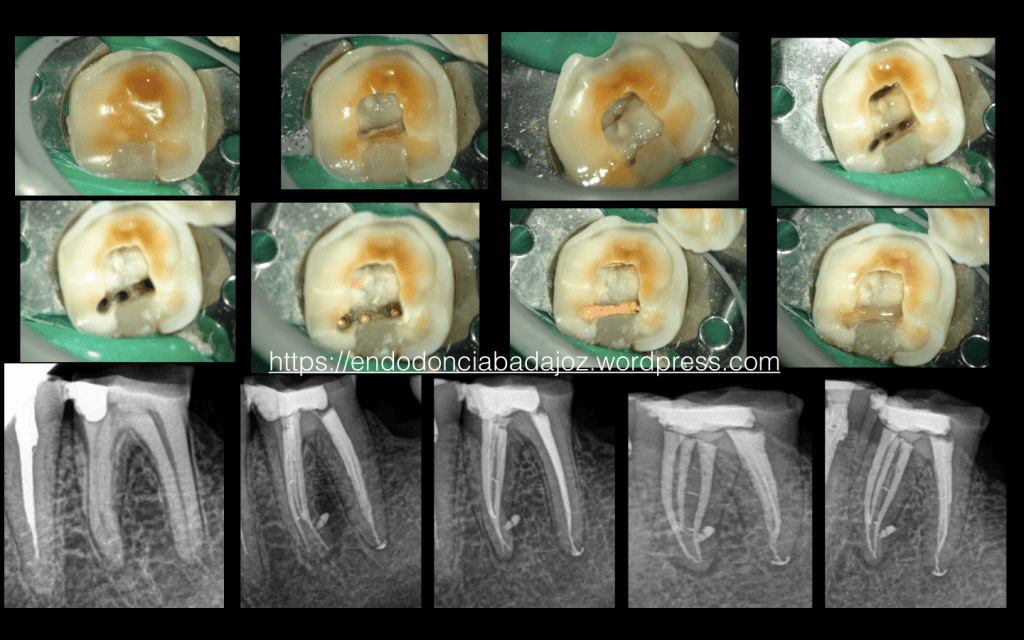

Cuidado con los istmos!!!

Es el caso de un tratamiento de un 3.6 en el que peligra, en ciertas ocasiones, esos restos de tejido orgánico que podemos dejar tras la instrumentación.